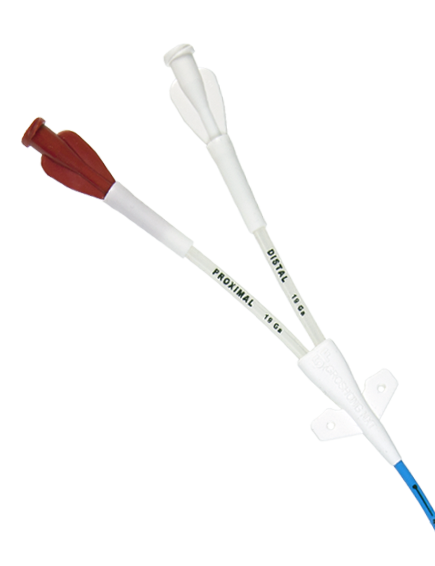

The Groshong® PICC, Proven performance coupled with proven effectiveness. For years Groshong® PICCs have set the standard in closed-system, vascular access delivery.